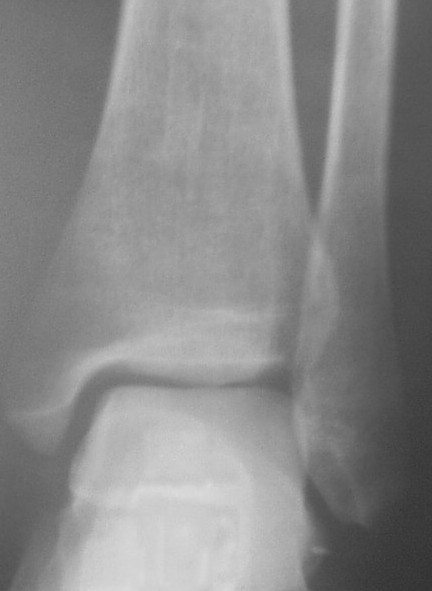

Трехчетвертной